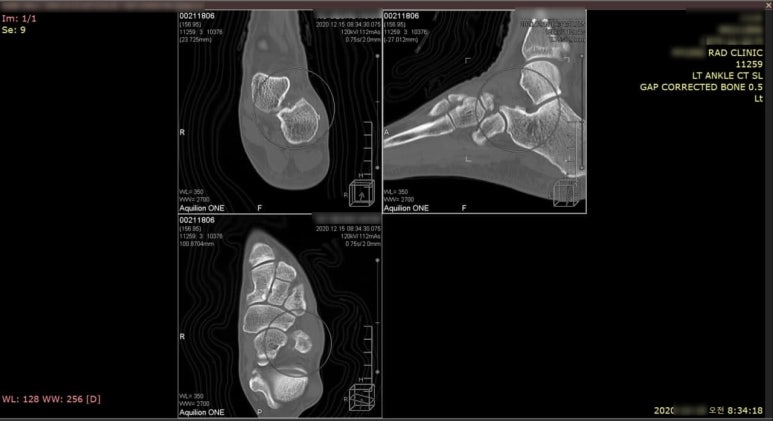

CT검사에서 뼈 조각을 발견

먼저 시행한 CT검사에서 과거 골절로 인한 뼈 조각이 발견되었습니다.

단순히 인대만 끊어진 것이 아니였던 것이죠. 인대가 늘어날 때 뼈를 잡아당기면서 뼈 조각이 떨어져 나와있었습니다.

골절이 있었던 곳인데 엑스레이상 골절이 잘 보이지 않는 부위이다보니 초기에 적절한 치료를 받지 못한 것입니다. 골절 진단을 받지 못한 상태로 고정하지 않고 움직이다보니 골절 부위가 점점 벌어집니다.

여러번 포스팅했지만 엑스레이에서 잘 보이지 않는 골절이 있습니다**. 미세골절, 견열골절, 비전위성 골절, 뼈가 겹쳐보이는 부위의 골절은 초기에 엑스레이에서 골절선이 잘 보이지 않습니다.

골절인지도 모르고 뭉친 것 같다고 열심히 스트레칭하고 움직이다보면 골절 부위가 벌어집니다. 벌어진 부위를 채우기 위해 가골이 크게 형성되는 후유증이 남게 됩니다.